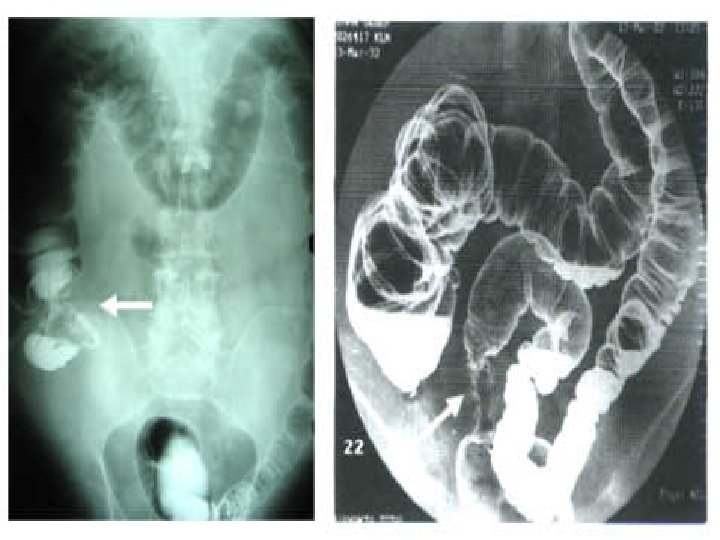

Kolorektal Kanserde Tanı • Abdominal BT (kitle, duvar kalınlaşması, çevreye invazyon, LAPler, KC metastazı) • Çift kontrast kolon grafisi (kitle, omuz işareti, yenmiş elma manzarası, rijidite, çift kontur, darlık, obstrüksiyon)

BARYUM ENEMA • >1 cm poliplerde duyarlılık %90 • Fleksible sigmoidoskopi ile beraber polipektomi ve kanser cerrahisi sonrası hastaları uzun dönem takibinde • Kolonoskopiyi tolere edmeyen hastalarda iyi bir alternatiftir. (F. sigmoideskopi ile) • Perforasyon %0. 02 dir.